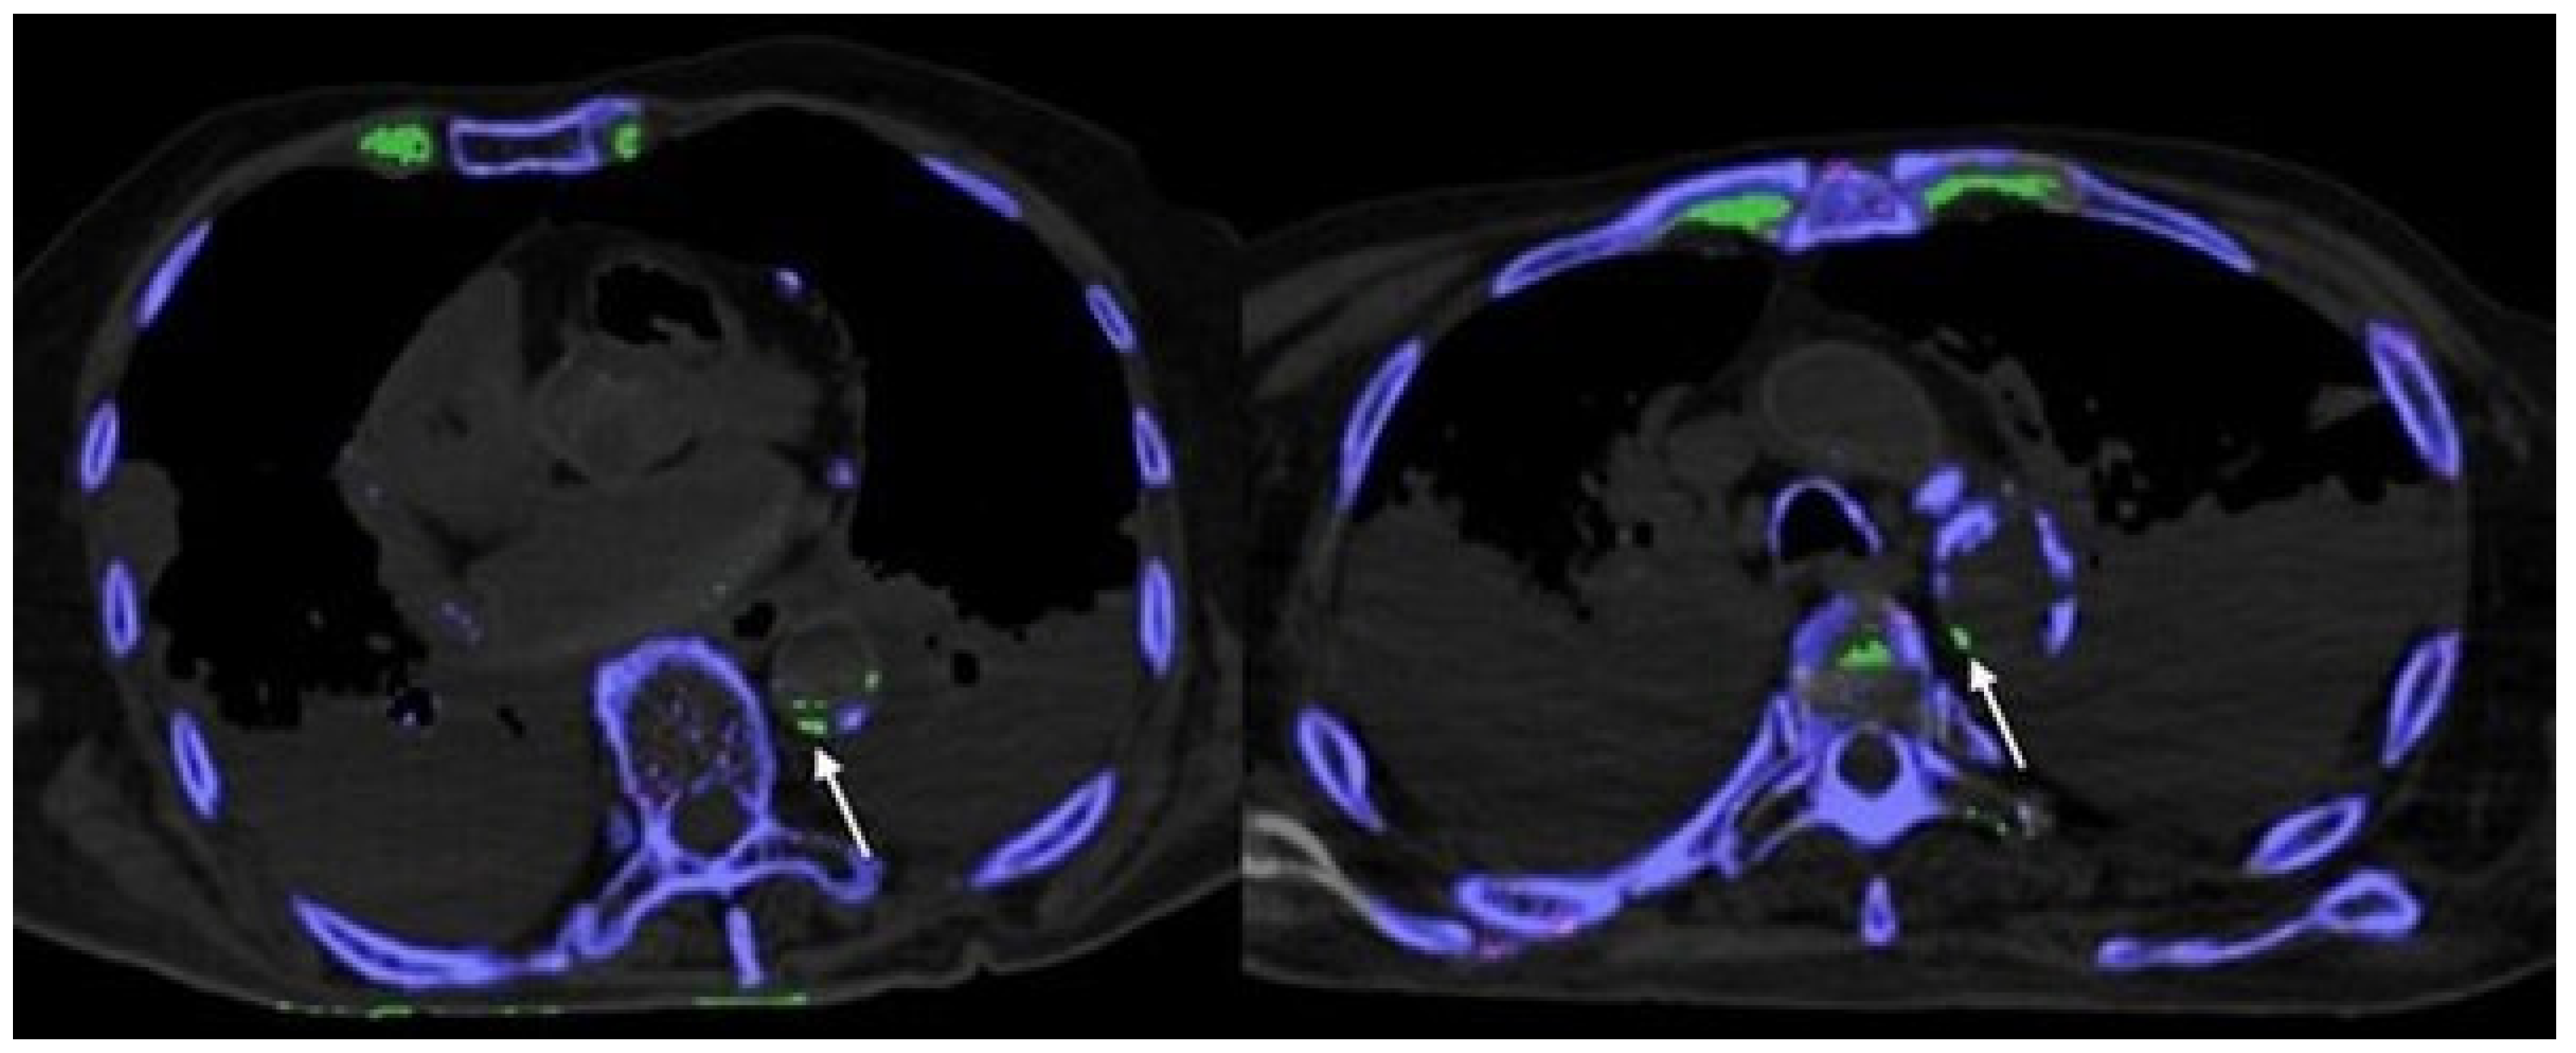

- Klauser, A.S.; Halpern, E.J.; Strobl, S.; Gruber, J.; Feuchtner, G.; Bellmann-Weiler, R.; Weiss, G.; Stofferin, H.; Jaschke, W. Dual-Energy Computed Tomography Detection of Cardiovascular Monosodium Urate Deposits in Patients With Gout. JAMA Cardiol. 2019, 4, 1019–1028. [Google Scholar] [CrossRef]